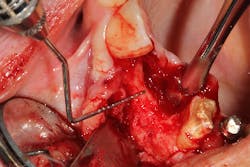

This patient presented with a long-standing edentulous area in the site of Nos. 6 and 7. She had lost both hard- and soft-tissue volume in the vertical and horizontal dimensions (figures 7 and 7a). Implant therapy was discussed as well as the option of multiple ridge augmentation procedures versus gingival ceramics. Although the patient has a low smile line, she was adamant about attempting to achieve a more proportional tooth length at final restoration. In addition, she complained about sensitive tissue underneath the pontic areas and an inability to clean her prosthesis. The periodontist and the patient decided to attempt to rebuild bony hard tissue and keratinized soft tissue. The patient understood the increase in finances and surgical procedures that would be involved.

The patient was referred to a periodontist who first augmented the edentulous site with a hard-tissue graft and membrane (figures 8 and 8a). Six months later, implants were placed in ideal positon (figure 9).